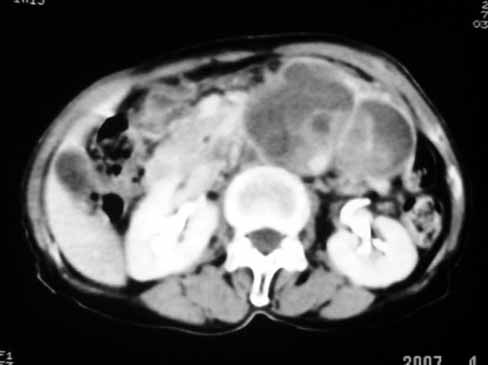

以下是引用天南地北在2007-4-30 17:42:00的发言:[br]增强扫描显示腹主动脉给包绕、推移。肿块不规则强化,[br]修正我在平扫的诊断[br]支持考虑:间叶源性肿瘤可能性大

以下是引用余辉在2007-4-30 18:01:00的发言:[br]病灶前方的条状增强影是什么?若是胰腺,位置似乎有点低,若是十二指肠,似乎又不诫该是那样强化,姑且将其看作胰腺吧,那么考虑来源于胰腺粘液囊腺瘤可能性大,其次考虑来源于肠系膜或者后腹膜的肿瘤如平滑肌肉瘤,异位嗜铬细胞瘤及淋巴瘤等。

以下是引用zyx168在2007-4-30 23:24:00的发言:[br]考虑:间叶源性肿瘤可能性大